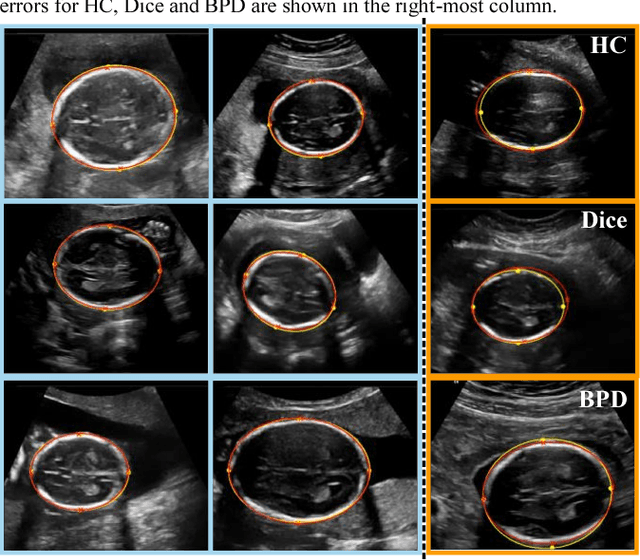

Abstract:Measurement of head biometrics from fetal ultrasonography images is of key importance in monitoring the healthy development of fetuses. However, the accurate measurement of relevant anatomical structures is subject to large inter-observer variability in the clinic. To address this issue, an automated method utilizing Fully Convolutional Networks (FCN) is proposed to determine measurements of fetal head circumference (HC) and biparietal diameter (BPD). An FCN was trained on approximately 2000 2D ultrasound images of the head with annotations provided by 45 different sonographers during routine screening examinations to perform semantic segmentation of the head. An ellipse is fitted to the resulting segmentation contours to mimic the annotation typically produced by a sonographer. The model's performance was compared with inter-observer variability, where two experts manually annotated 100 test images. Mean absolute model-expert error was slightly better than inter-observer error for HC (1.99mm vs 2.16mm), and comparable for BPD (0.61mm vs 0.59mm), as well as Dice coefficient (0.980 vs 0.980). Our results demonstrate that the model performs at a level similar to a human expert, and learns to produce accurate predictions from a large dataset annotated by many sonographers. Additionally, measurements are generated in near real-time at 15fps on a GPU, which could speed up clinical workflow for both skilled and trainee sonographers.